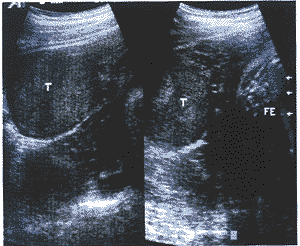

中国超声医学杂志990743 患者,女性,24岁。因怀孕后全身多毛、面貌改变26周入院。患者停经2个月左右出现 声音嘶哑,孕三个月左右出现痤疮、胡须、全身多毛。查体除上述表现外,尚可见皮肤色较 黑、乳晕不着色、腹无紫纹,考虑为雄激素增高所致。血激素检查:FSH 18.6mIU/ml, LH 180mIu/ml,PRL>200ng/ml,Ez>2000pg/ml,T>2000ng/dl,P>100ng/ml,即T(雄 激素)明显增高,应用Domier AI-5200型彩多普勒超声诊断仪,探头频率为5MHz,超声检查 表现:耻上见胎头,双顶径73mm,见胎心胎动,股骨长53mm,胎盘位于后壁,厚28mm,羊水 最大前后径50mm。子宫右侧附件区见50mm×52mm×65mm稍强实质肿块回声,边界清,有包膜 ,内回声欠均匀(图1),左侧附件区未见明显肿块回声。CDFI:胎儿脐带血流A/B比值为3.8 ,右侧附件肿块周边及内部均见丰富的彩色血流,呈红蓝相间的点、条状彩色血流回声(图2 ),肿块一动脉频谱为Vmax 55cm/s,Vmin 31cm/s,RI 0.43,为高速低阻血流(图3)。超声 提示:1.右侧附件实质性肿块(具分泌功能之卵巢肿瘤);2.单胎头位。患者继续怀孕至38 W+2天,行剖腹产及卵巢肿瘤切除术,剖出一正常男婴,出生时有轻度窒息,羊水 过少。术中见右卵巢肿瘤大小6cm×5cm×4cm,包膜完整,质硬。病理诊断:(右)附件卵巢 支持-间质细胞瘤(高、中度分化)。肿瘤部分区域瘤组织呈腺瘤状结构,衬以葵花子样核的 支持细胞,大部分区域呈片状排列的间质细胞。

T:肿块,FE:胎儿

图1 妊娠并右侧卵巢睾丸母细胞瘤